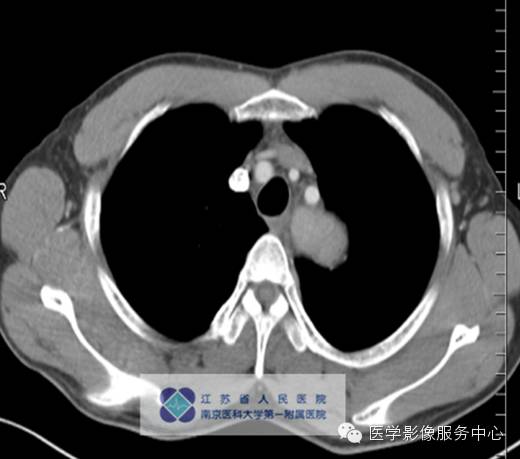

影像分析:左上、后纵隔内见类圆形软组织密度增高影,密度尚均匀,边缘清晰,增强扫描均匀强化。

单中心型:大部分为透明血管型,表现为纵隔及肺门圆形或卵圆形较大软组织肿块,边缘光滑锐利可有分叶,多数密度均匀可伴斑点状、树枝状等不同表现钙化。Meador等报道病变强化与病灶大小有关,小于5cm多为均匀强化,大于5cm的多不均匀强化,另外,还与病变的组织学特点如变性、坏死、纤维化的程度有关。

平衡期病灶持续强化,呈略高或高密度。外周有点状异常增强的小血管,可能滤泡间大量毛细血管增生,周围有滋养血管所致。